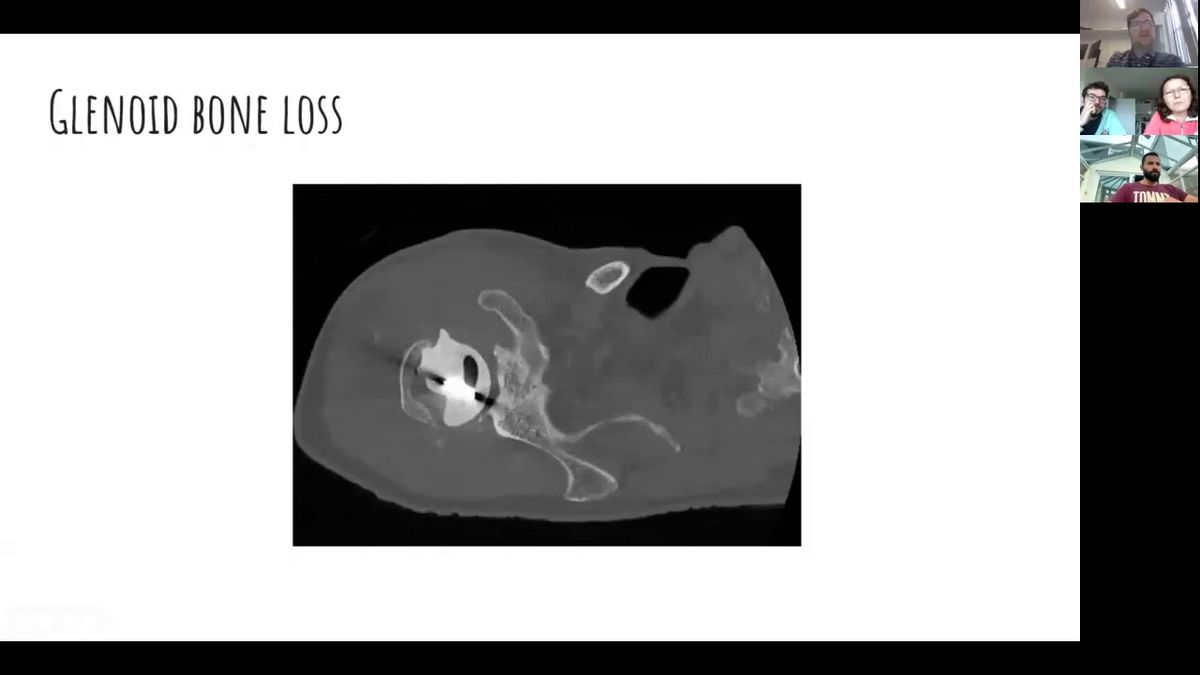

OK. Right. Say uh when we left off, uh we were just, er, we've done glenoid, er, kind of failure. So, as we said, the main issue is really around either it being infected aseptically loose or it's a mechanical failure of the implant in terms of the Rocker horse phenomenon. Ok. So what about the humerus? How can the humerus fail? All right. So I put on three different implants there. Can anyone tell me the difference between, particularly the stemmed ones? Can you see anything different about the, the stems? Left? One looks like it's metal on metal. One is fully coated and one is just coated. One looks fenestrated, I guess for uh suture. I'm not sure why that is anyone else let Maria see if she can get her mic working? But I think is it, is it fully versus? Ok. Approximately, can anyone else see a difference between the stems? I think Maria's m thing is not working. So what I said was that one is just approximately coated. I still can't hear him and the other one is fully coated. Can you hear me? They just me? They can't hear me and, and II think it's just, you can, you, can you hear me? No, he can't hear anyone that's on the, oh, you can hear me here. Oh, I can't, I don't know where that is. Um, let me just check also on the left screen. Uh, these are humorous implants on the right one. These are stemless. Sorry about this. Yeah. Mm. So, my speakers are working. Can anyone else? Hey, me or we, we hear you, We hear you loud and tired. Do you hear of anybody? No, no. Ok. Um. Oh, you can hear me. That's good. Sherry. Ok. Um, all right. I don't know. Does anyone have any ideas how we're gonna get around that or do you want me to, what do you think is best for you, Ben? Do you want to? I can see the chat so I log in, log out. Kare says, ok, I'll try that. Bear with me.